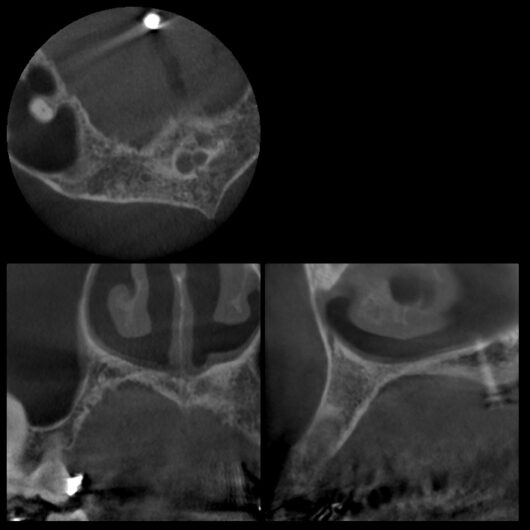

初診時レントゲン・CT

膿が大きく認められました。

「前歯の違和感」という主訴に対して、まずは客観的な評価が必要です。今回、以下の検査を実施しました。

検査の結果、インプラント周囲の骨の状態、インプラント体の位置、周囲組織の状態など、すべてにおいて問題は認められませんでした。これは、8年間適切にメインテナンスを継続してきた成果と言えるでしょう。